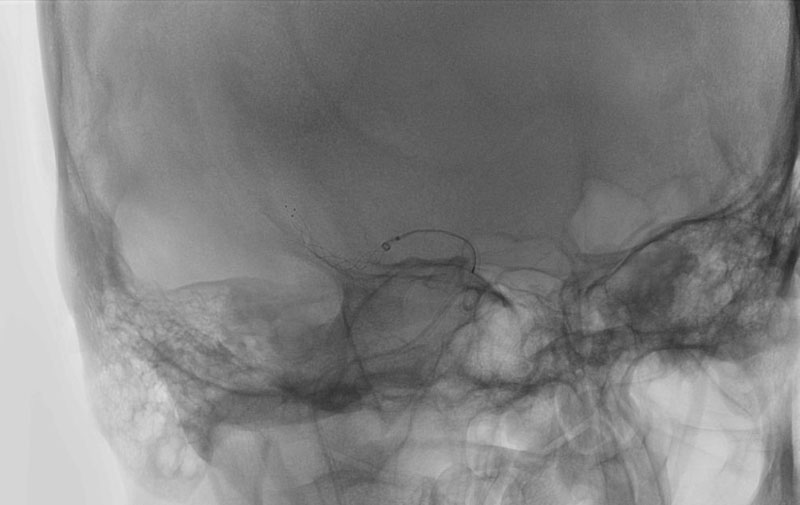

左椎骨動脈後下小脳動脈分岐部動脈瘤

70代

院内外来

No.1628 手術中

No.1628 手術後